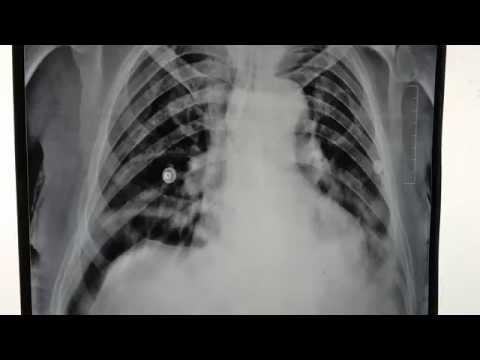

이 분은 78세의 사나이다. 만성 소화 불량으로 몇년 전부터 필자가 담당하는 분이라고. 2012년 담낭 담석이 하나 있고 담낭 절제를 하고 가슴이 아프다며 그 후에 관상 동맥 ct를 시행하고 약 50%관상 동맥의 협착이 있다고 했으나 그 이상의 조치는 하지 않았다. 역류성 식도염으로 투약하고 대체로 현재까지 잘 견디고 계신다. 최근 이 분의 다양한 사진을 검토하는 과정에서 위 사진처럼 횡격막과 간의 사이에 대장이 끼어 있는 것이 관찰됐으며 이 마직 막 사진에서는 그 부분의 대장에는 장의 작은 마비를 시사하는 수면(fluid level)를 가리키고 있혹시 이 분의 증상이 이른바 Chilaiditi증후군은 아닌지 의심스럽다. 이 분처럼 대장이 횡격막과 간의 사이에 끼는 현상을 Chilaiditissign. 이것이 확실히 증상을 부를 확인되면 Chilaiditi증후군으로 진단한다. 그러나 이 병은 감염이 매우 어려운 증상도 다양하다. 이 병은 19010년에 그리스의 방사선 의사인 Dimitrios Chilaiditi가 처음 기술했다. 뚜렷한 증상은 오른쪽 위 복부가 아프지만 다른 병이 설명할 수 없고 이런 현상을 보이면 이 병을 의심한다. 그러나 대장이 이 사이에 끼어 보이는 경우는 비교적 적지 않아 만약 간 경변증이 심하면 간이 위축되고 이런 가능성이 있다고 불리는 이 현상을 보이면 간 질환을 의심하고 보는 정도였다 만약 앞으로 이런 현상을 보이는 분들을 보면 관심을 갖고 검토할 필요가 있다고 생각한다.